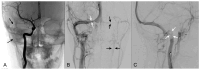

Results: A 6-year-old patient was admitted for right otomastoiditis and thrombosis of the sigmoid and transverse sinuses, as well as the proximal portion of the internal jugular vein. Radiological examinations revealed a left orbital mass (22 × 14 mm) compatible with asymptomatic orbital meningocele (MC) herniated from the superior orbital fissure (SOF). The child underwent a right mastoidectomy. After the development of symptoms and signs of intracranial hypertension (ICH), endovascular thrombectomy and transverse sinus stenting were performed, with improvement of the clinical conditions and reduction of the orbital MC. The systematic literature review encompassed 29 publications on 43 patients with spontaneous orbital MC. In the majority of cases, surgery was the preferred treatment.